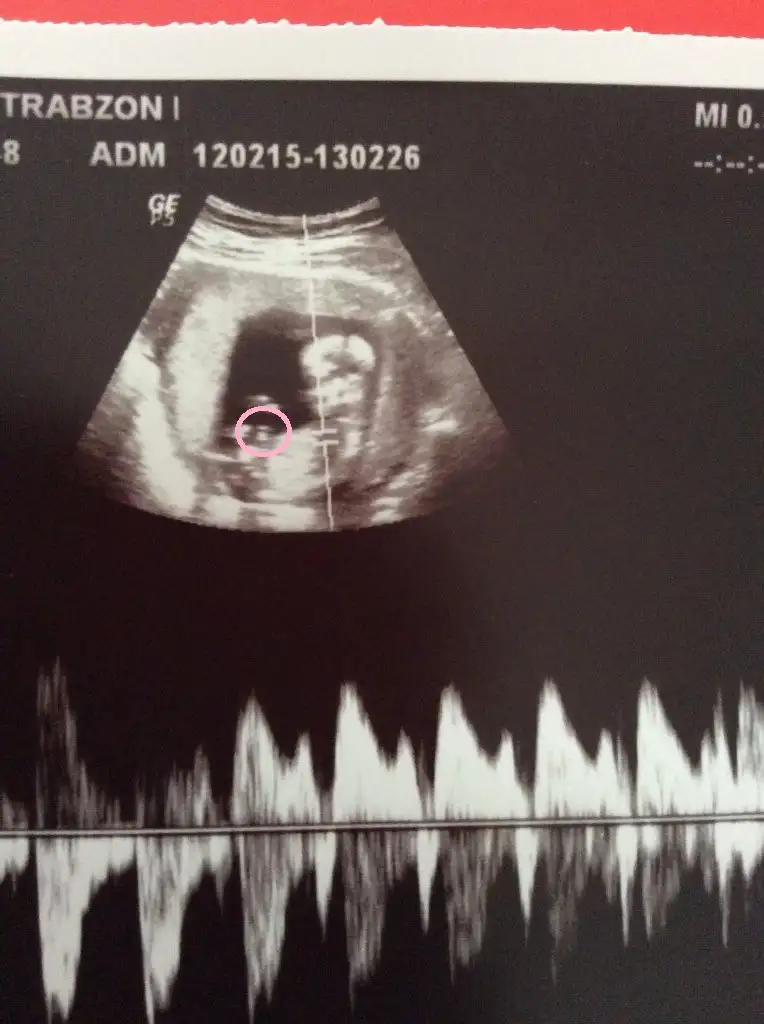

hadi baalım hayırlısı benimde içime hep erkek doğuyor :)erkek gibi görüyorum

Yani? Kusura bakmayın anlamıyorum :)Eki Görüntüle 1413396 BU GÖRDÜĞÜMÜZ NUB İSE BAYA DİK :)))))))))) ÖBÜR RESİMDEN BİŞEY ANLAMADIM...

DİK OLURSA ERKEK PARALEL OLURSA KIZ OLUYORMUŞYani? Kusura bakmayın anlamıyorum :)

DİK OLURSA ERKEK PARALEL OLURSA KIZ OLUYORMUŞEki Görüntüle 1413434